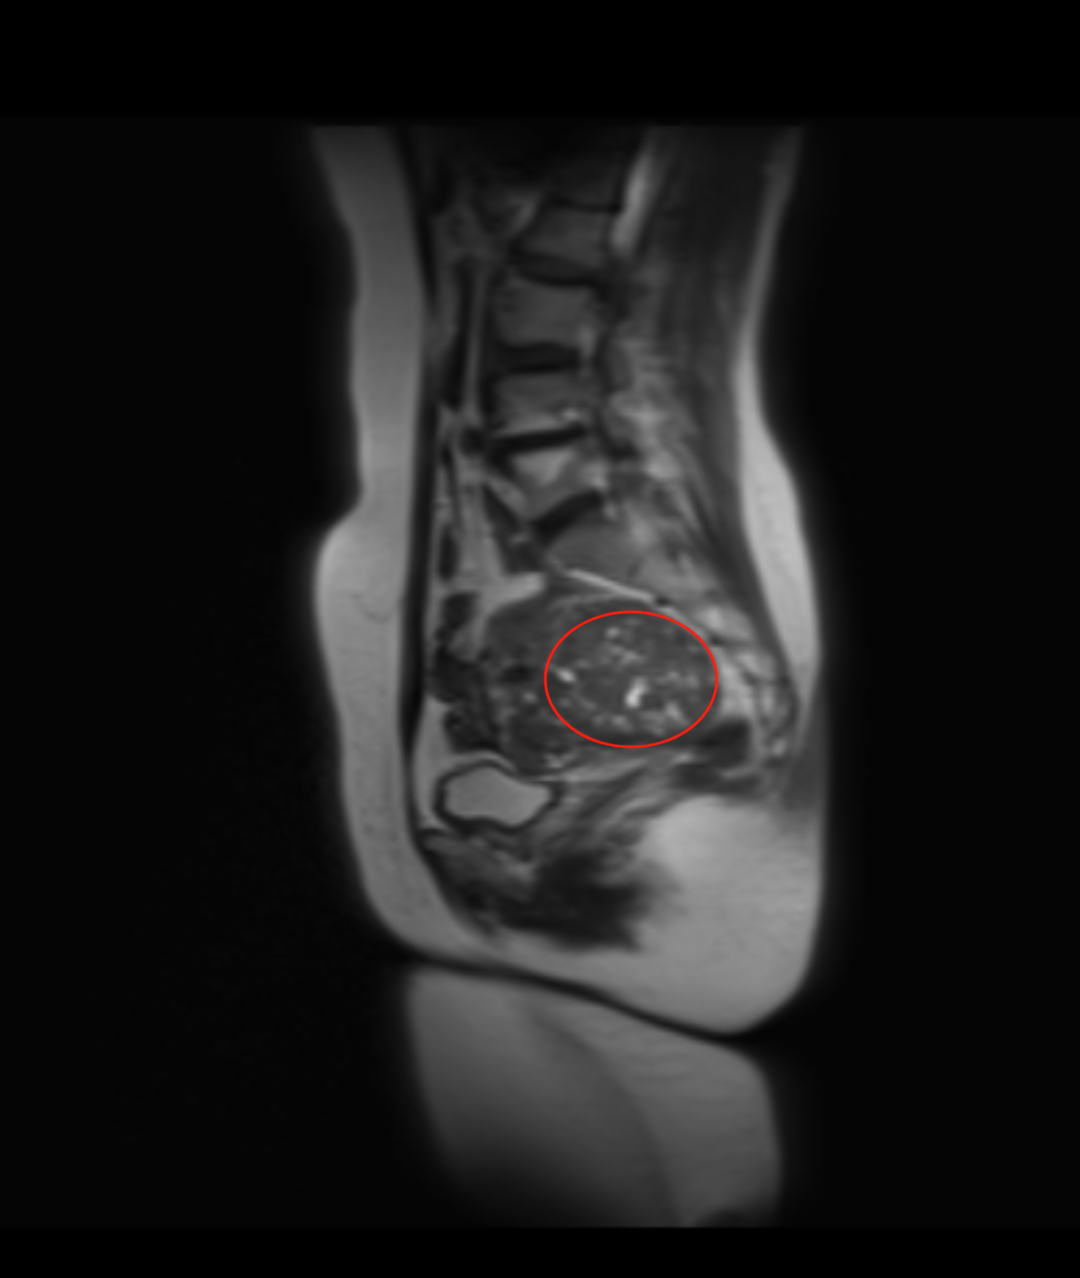

入院后,妇科团队为戴阿姨完善了盆腔增强 MRI、肿瘤标志物、性激素六项等相关检查。结合影像学特征和实验室结果,初步诊断为「子宫阔韧带良性肌瘤」。徐彩临院长带领妇科医护团队立即展开病例讨论:患者 53 岁,处于围绝经期,肌瘤体积较大(直径超 10 cm),虽考虑良性,但已可能压迫周围脏器,且存在潜在生长风险,符合手术指征。最终确定腹腔镜下右侧阔韧带肌瘤剔除术为首选方案,但手术难度大。